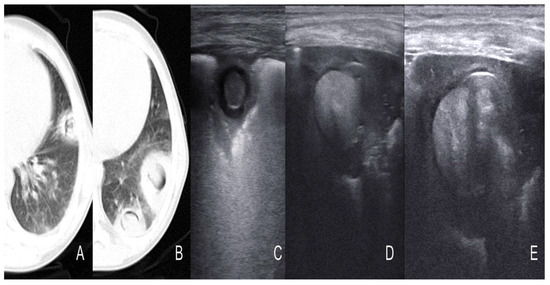

- Ruby, L.C.; Kadavigere, R.; Sheshadri, S.; Saravu, K.; Bélard, S. Pulmonary aspergilloma on transthoracic ultrasound. Infection 2021, 49, 1337–1340. [Google Scholar] [CrossRef]

- Rea, G.; Sperandeo, M.; Lieto, R.; Bocchino, M.; Quarato, C.M.I.; Feragalli, B.; Valente, T.; Scioscia, G.; Giuffreda, E.; Foschino Barbaro, M.P.; et al. Chest Imaging in the Diagnosis and Management of Pulmonary Tuberculosis: The Complementary Role of Thoracic Ultrasound. Front. Med. 2021, 8, 753821. [Google Scholar] [CrossRef]

- Giannelli, F.; Cozzi, D.; Cavigli, E.; Campolmi, I.; Rinaldi, F.; Giachè, S.; Rogasi, P.G.; Miele, V.; Bartolucci, M. Lung ultrasound (LUS) in pulmonary tuberculosis: Correlation with chest CT and X-ray findings. J. Ultrasound 2022, 25, 625–634. [Google Scholar] [CrossRef]